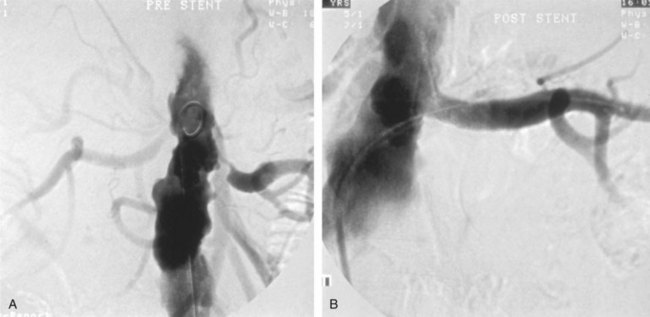

The arteriogram in perimedial fibroplasia may give the appearance of arterial beading, but careful observation shows that the caliber of the normal segment of the vessel is not exceeded by the “bead” (Fig. 39–6). This fact, along with the frequent occurrence of extensive collateral circulation, differentiates this lesion angiographically from that of medial fibroplasia. Perimedial fibroplasia produces severe stenosis, and, although complicating thrombosis or dissection is relatively uncommon, progressive obstruction with ischemic renal atrophy occurs in almost all patients managed nonoperatively.

Figure 39–6 Renal arteriogram in a patient with perimedial fibroplasia shows slightly irregular, yet severe, stenosis of the midrenal artery (arrows) associated with extensive collateral circulation to the kidney. The small size of the arterial irregularities and the presence of collateral circulation distinguishes this lesion radiographically from medial fibroplasia.

(From Novick AC. Renal vascular hypertension in children. In: Kelalis PP, King LR, Belman AB, editors. Clinical pediatric urology. Philadelphia: WB Saunders; 1984.)